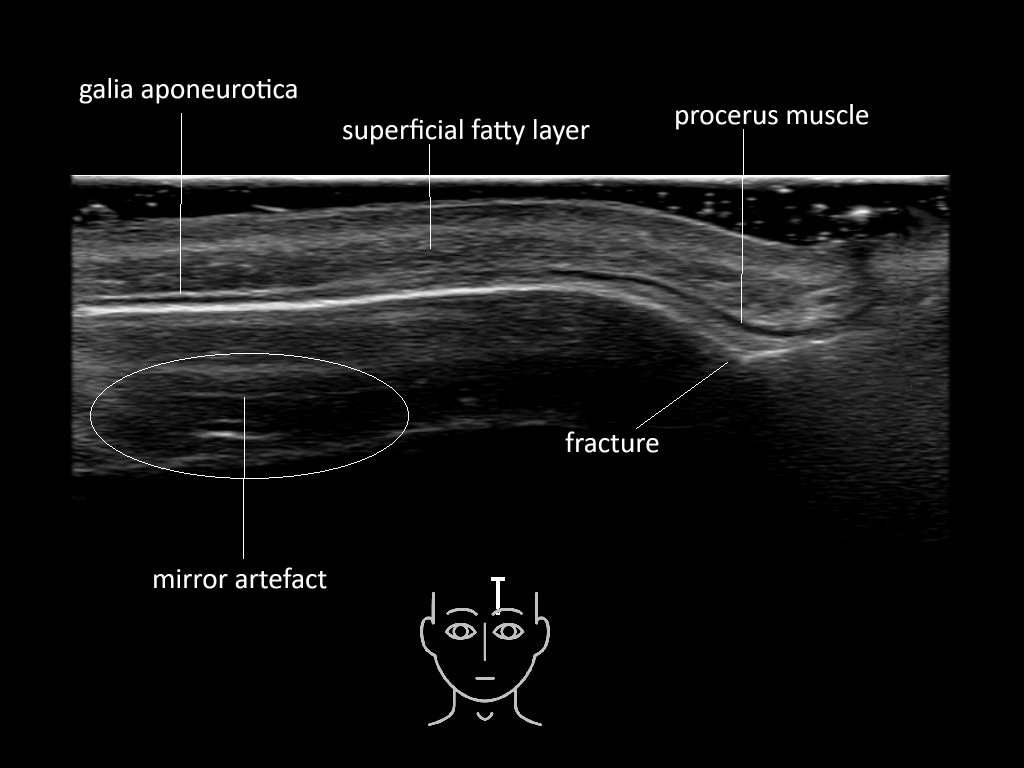

In this section you will learn more about the different layers of the face with the use of ultrasound. When you click on the secondary ultrasound image, you will see the different structures as an overlay. This will help to train yourself to recognize the different layers of the face.

Study the first image to recognize the different layers. If you are sure about the layers, swipe to the second image to view the answer (if applicable).